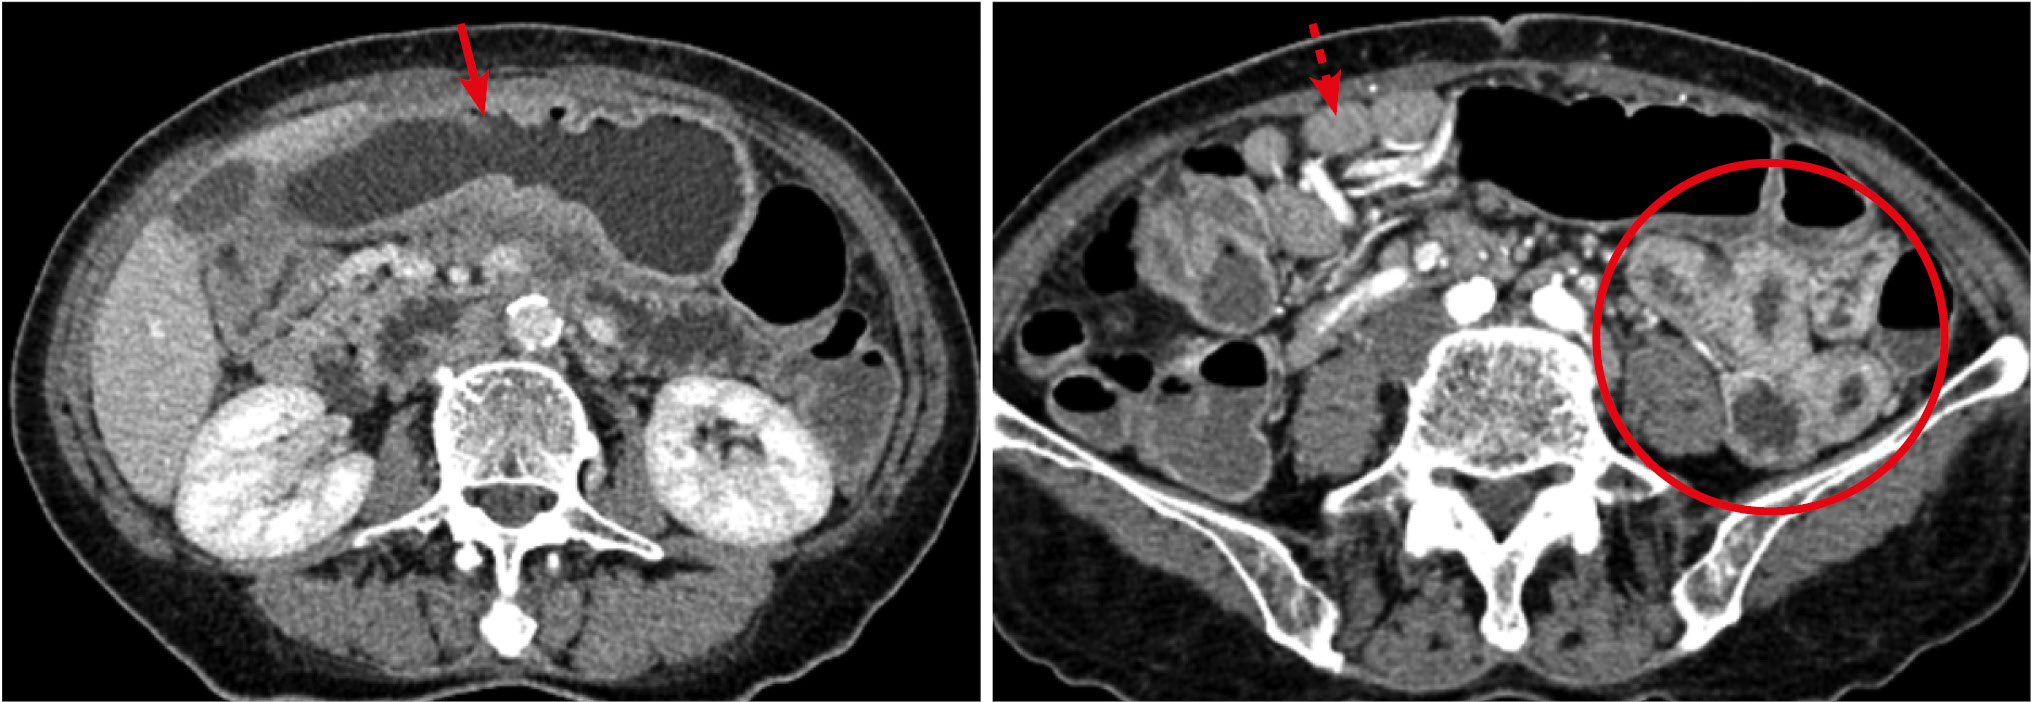

Рис. 1. Больной, 34 года. МСКТ: болезнь Крона желудка, тонкой и толстой кишок с поражением желудка, терминального отдела подвздошной и слепой кишок. Хроническое рецидивирующее течение, осложненное кишечной непроходимостью, тяжелая форма, высокая активность, фаза обострения. Артериальная фаза контрастного усиления

Примечание. Определяются множественные утолщения стенки тонкой кишки (стрелки), вызывающие сужение просвета. Стенка в местах утолщения накапливает контрастный препарат по слоистому типу с повышенным контрастным усилением внутреннего и наружного слоев (стрелки). Между расширенными петлями кишки заметно скопление свободной жидкости.

Повышенное контрастное усиление стенки пораженных участков — второй характерный признак болезни Крона ТК. Тип и степень контрастного усиления напрямую зависели от фазы воспаления. Фаза активного воспаления характеризовалась одно- или двухслойным слоистым контрастным усилением за счет яркого фона слизистой оболочки и отека подслизистого слоя соответственно с формированием картины одно-/двухслойного расслоения или стратификации (рис. 2). В прилежащей части брыжейки определялись подчеркнутый сосудистый рисунок с минимально расширенными просветами (симптом «расчески»), вдоль сосудов брыжейки определялись увеличенные лимфатические узлы. Структура лимфатических узлов была однородна, контур ровный и четкий, поперечный размер чаще (89%) не превышал 10 мм.

Рис. 2. Больная, 34 года. МСКТ: болезнь Крона, множественное поражение тонкой и толстой кишки. Артериальная фаза контрастного усиления. Фрагменты аксиальных томограмм

Примечание. Определяется сегментарное утолщение стенки ТК (стрелки) и нисходящей ободочной кишки (пунктирная стрелка). При контрастном усилении наблюдается трансмуральное контрастное усиление стенки и усиление сосудов брыжейки (обозначено кругом).

В фазу ремиссии болезни Крона контрастирование стенки характеризовалось трансмуральным утолщением и слоистостью на фоне развития фиброзных изменений в подслизистом слое и повышенного контрастного усиления слизистой оболочки (рис. 3, А) или отложением жировых включений в подслизистом слое (рис. 3, Б).

Рис. 3. МСКТ: болезнь Крона, стадия неполной ремиссии

Примечание. А — артериальная фаза контрастного усиления: определяется трехслойная структура стенки терминального отдела подвздошной кишки (стрелка) за счет развития фиброзных изменений в подслизистом слое и повышенного контрастного усиления слизистой оболочки. Б — больная в возрасте 67 лет: болезнь Крона, стадия ремиссии; нативное исследование: трехслойная структура стенки терминального отдела подвздошной кишки объясняется отложением жировых включений в подслизистом слое (стрелка).